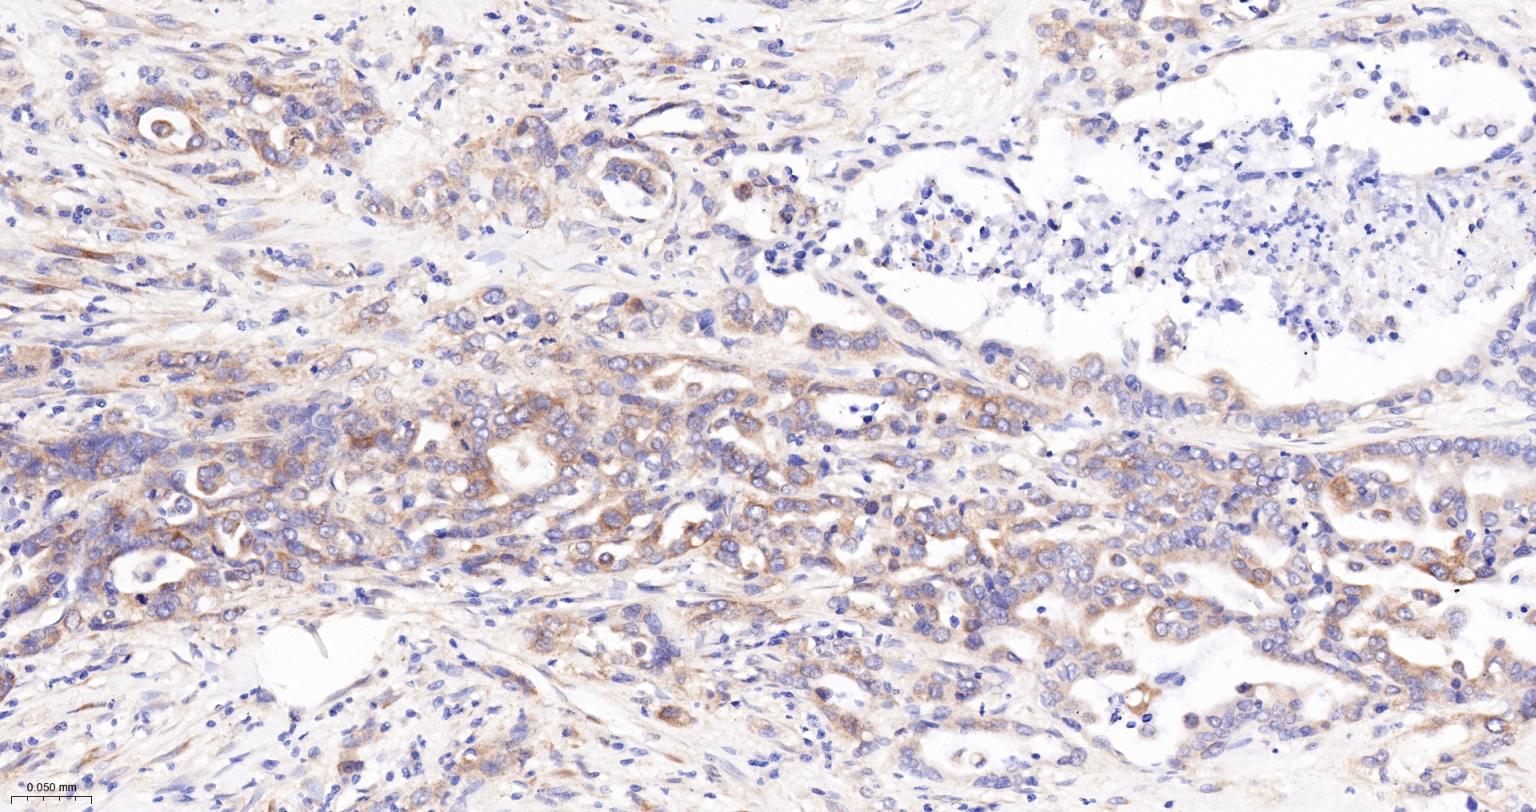

Paraformaldehyde-fixed, paraffin embedded Human Ovarian Cancer; Antigen retrieval by boiling in sodium citrate buffer (pH6.0) for 15 min; The section was incubated with Radixin Monoclonal Antibody, Unconjugated (bsm-61253R) at 1:200 overnight at 4°C, followed by conjugation to the bs-0295G-HRP and DAB (C-0010) staining.

Paraformaldehyde-fixed, paraffin embedded Human Liver Cancer; Antigen retrieval by boiling in sodium citrate buffer (pH6.0) for 15 min; The section was incubated with Radixin Monoclonal Antibody, Unconjugated (bsm-61253R) at 1:200 overnight at 4°C, followed by conjugation to the bs-0295G-HRP and DAB (C-0010) staining.